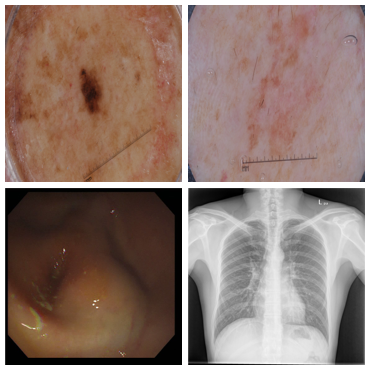

Improved Inference via Deep Input Transfer

Saeid Asgari Taghanaki, Kumar Abhishek, Ghassan Hamarneh

International Conference on Medical Image Computing and Computer Assisted Intervention (MICCAI), 2019

(Early Accept)

We propose an input image transformation technique that relies on the gradients of a trained segmentation network to transform the images for improved segmentation performance. [Abstract] [BibTeX]

Although numerous improvements have been made in the field of image segmentation using convolutional neural networks, the majority of these improvements rely on training with larger datasets, model architecture modifications, novel loss functions, and better optimizers. In this paper, we propose a new segmentation performance boosting paradigm that relies on optimally modifying the network's input instead of the network itself. In particular, we leverage the gradients of a trained segmentation network with respect to the input to transfer it to a space where the segmentation accuracy improves. We test the proposed method on three publicly available medical image segmentation datasets: the ISIC 2017 Skin Lesion Segmentation dataset, the Shenzhen Chest X-Ray dataset, and the CVC-ColonDB dataset, for which our method achieves improvements of 5.8%, 0.5%, and 4.8% in the average Dice scores, respectively.